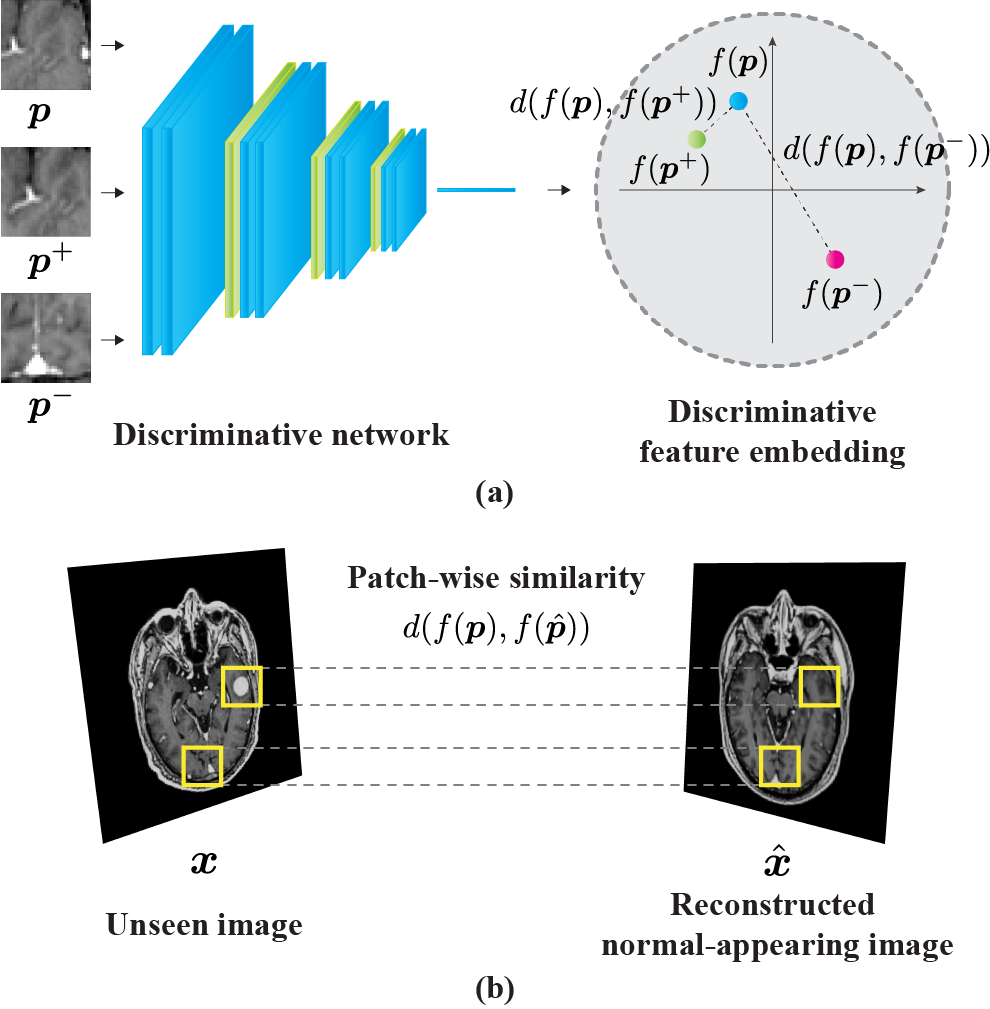

II-C Discriminative Network

Whereas the reconstruction network learns the normal anatomy of the entire image, the discriminative network learns the pattern of the patch-level normal appearance based on metric learning. The discriminative network is essential for detecting abnormalities by comparing query images with reconstructed normal-appearing images.

At the training stage, for every randomly cropped patch from the normal images, a triplet of patches is prepared (Fig. 2a). Positive patches are obtained from small random affine translations around the original patch and small changes in the image intensity and range. Negative patches are created by random cropping from the same images. The discriminative network learns discriminative embeddings using the triplet margin loss [28] as follows:

| (8) |

where is the L2 distance between two embedded features.

When detecting abnormalities in unseen images, the patch-wise similarity of embedded features between input images and reconstructed images is calculated by the reconstruction network using the L2 distance (Fig. 2b). We considered the similarity measure as the abnormality score of the center pixel in each patch. The distribution of abnormality scores per image was standardized using Z-score normalization. As the reconstruction network reproduces the normal-appearing image more faithfully, the contrast with the abnormal part in the unseen image becomes clearer, and the detection performance using abnormality score can be expected to improve.